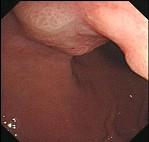

问题 男性54岁,间歇性上腹部不适4年,餐后加重,嗳气来诊。胃镜检查如图,应采取下列哪种治疗方法为宜 ( )

选项 A.西咪替丁 B.吗丁啉 C.吗丁啉+法莫替丁 D.洛赛克 E.手术治疗

答案 E